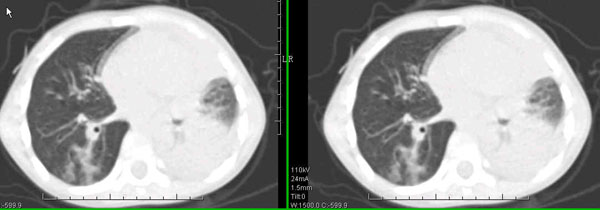

男孩,4岁,发热咳嗽4天。

下面补充ct图片:

此病人是我接手的,发热、咳嗽来做胸透,透视见左侧肺野大部密实,纵隔、心影明显左移,呼吸示纵隔摆动、膈肌矛盾运动(透视下采集了几幅图片),左肺动度明显减弱。询问病人家长,没有吃花生米等呛咳史。由于其影像特征明显,当时诊断:考虑左侧支气管异物并阻塞性肺不张、肺炎。

病人去上级医院支气管镜取出了异物。今天询问上级医院耳鼻喉科主任(是我同学),得知病人异物为胶冻样合并有少许白色粉末,后小儿说晚上喝药片时呛咳过,考虑当时为药片阻塞;另外支气管镜检发现小儿左侧支气管发育略窄,经住院抗炎治疗,现病人基本康复。

多谢各位关注及精彩点评!追踪病人结果时才知道还做过ct检查!对不起!有点晚了,刚刚下载,上传供大家参考!